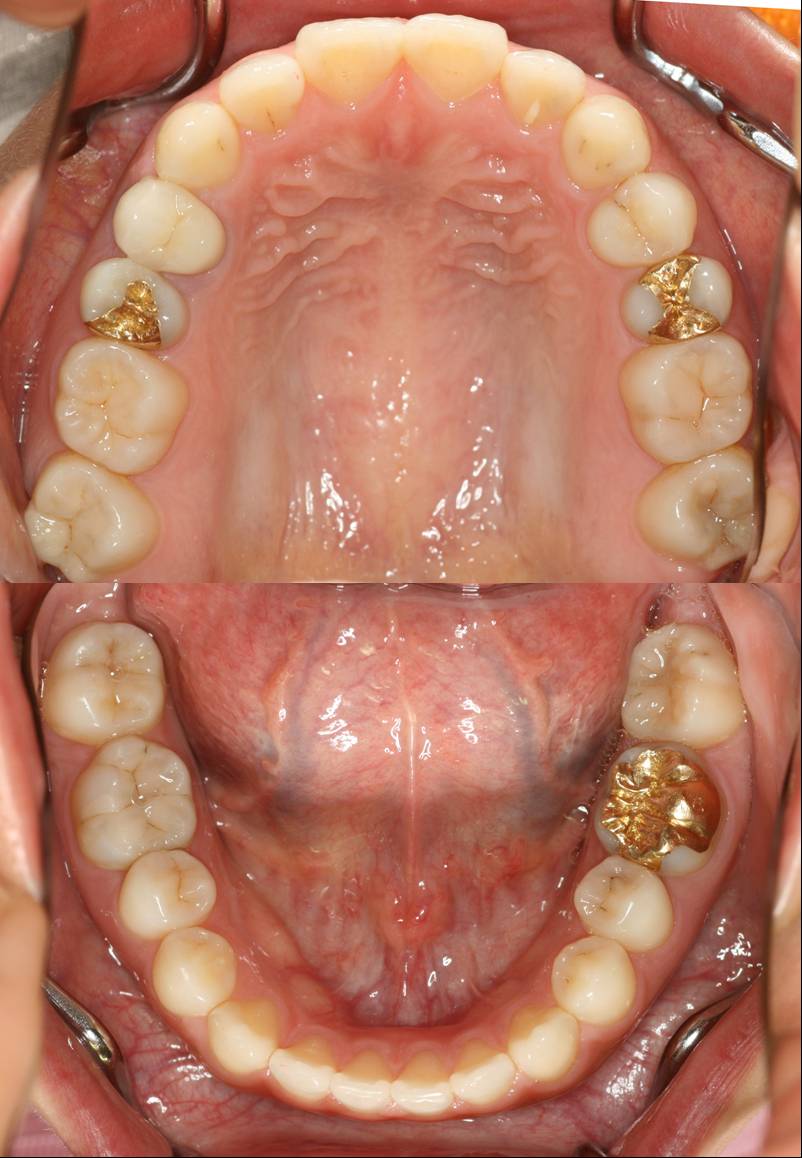

今年ベスト3に確実に入る治療ですから難易度高いです。

さて、何箇所治したでしょう!?(;¬_¬)

レジン  ○本  ゴールド 3本  オールセラミック 1本

答えは、

レジン治療11本でした